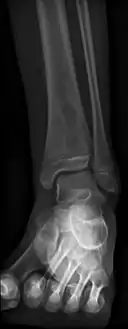

Oval, elliptical, or serpentine radiolucency usually greater than 1 cm surrounded by a heavily reactive sclerosis, granulation tissue, and a nidus often less than 1 cm. The margins often appear scalloped on radiograph. Brodie's abscess is best visualized using computed tomography (CT) scan. Associated atrophy of soft tissue near the site of infection and shortening of the affected bone. Osteoblastoma may be a classic sign for Brodie's abscess.

Periostial reaction along the medial cortex indicates an aggressive lesion. Neoplasm such as Ewing sarcoma and osteomyelitis could both have this plain radiographic appearance. Staphylococcus was recovered at surgery. Periostial reaction along the medial cortex indicates an aggressive lesion. Neoplasm such as Ewing sarcoma and osteomyelitis could both have this plain radiographic appearance. Staphylococcus was recovered at surgery.